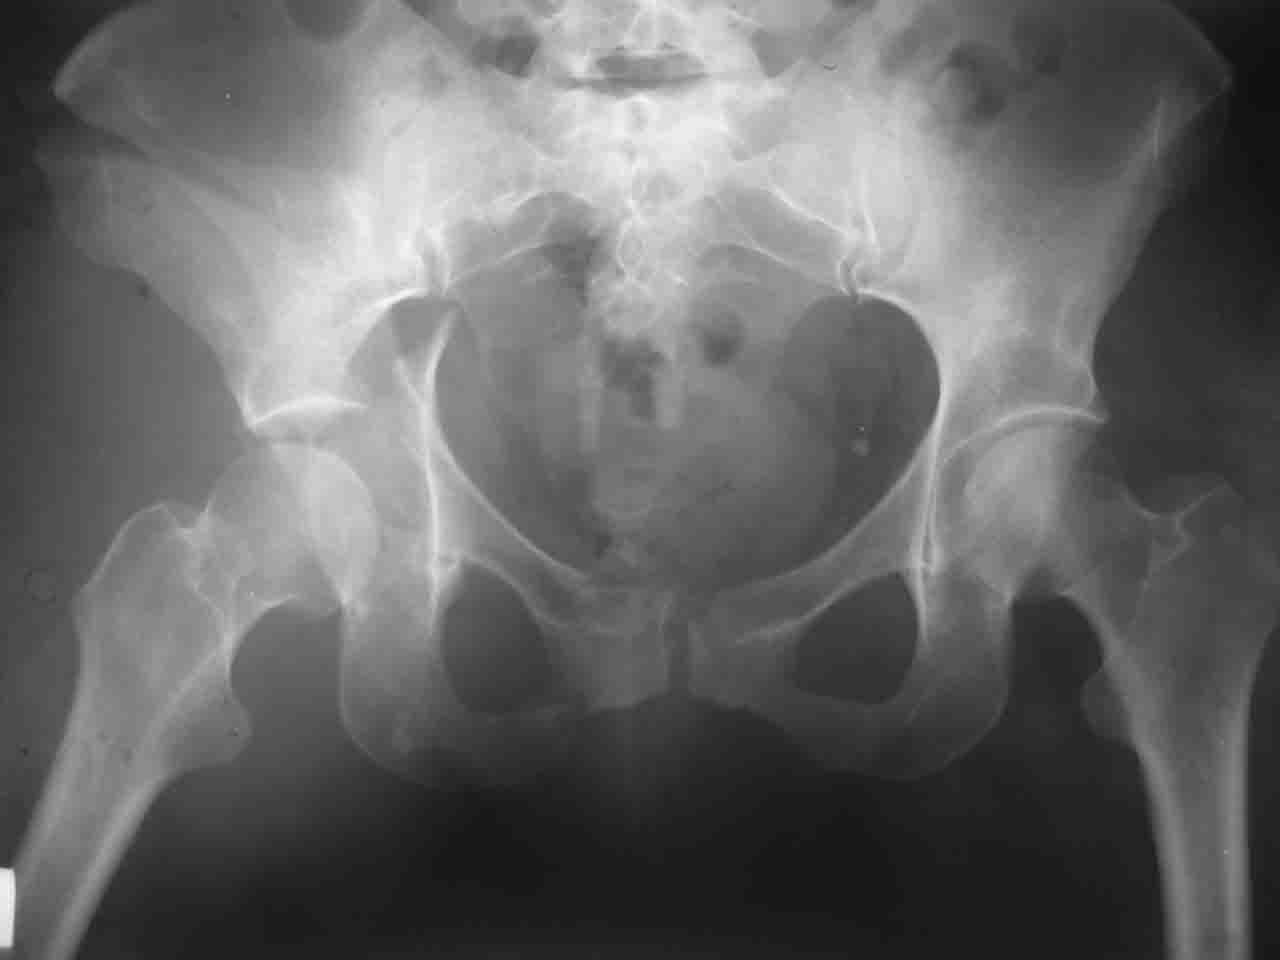

Вопрос доступа к вертлужной впадине при остеосинтезе задача не простая. Конечно, у Летурнеля и Тайла всё давно описано, нам остается только брать на вооружение. Но сами понимаете, что не бывает двух одинаковых ситуаций, поэтому в каждом случае вопрос решается сугубо индивидуально. Наша главная цель - восстановить анатомию с нанесением минимальной дополнительной травмы тазобедреннному суставу, думаю с этим никто не поспорит. Расширенный илиофеморальный доступ уж слишком травматичен (как сказал один коллега "таз лежит отдельно, больной отдельно").Стоит ли делать из пациента анатомический препарат для того чтобы легче ориентироваться. Да и нужно ли собирать всю "мозаику"? Мы применяли при таких операциях своеобразную операционную хитрость - сначала устраняли грубое смещение крыла под гребнем с фиксацией так называемой "плавающей" пластиной (временно фиксированной на двух винтах)- доступ или продлевали боковой, или делали небольшой дополнительный разрез над гребнем. Это позволяло устранить грубое смещение и захождение отломков тела повздошной кости, что значительно облегчало репозицию и остеосинтез впадины над сводом. Основное внимание конечно же уделяли нагружаемому задне-верхнему отделу. Сообщите ваш адрес, пришлю схемы и рентгенограммы.